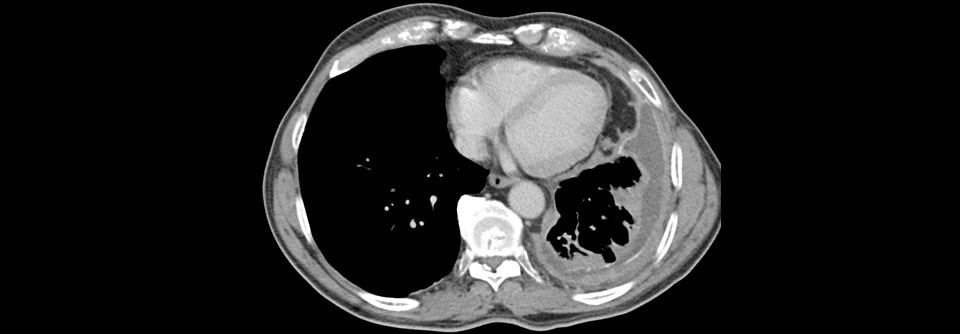

Immuncheckpoint-Inhibitoren haben sich bei der Behandlung des nicht-resektablen Pleuramesothelioms weitgehend bewährt. Immuncheckpoint-Inhibitoren haben sich bei der Behandlung des nicht-resektablen Pleuramesothelioms weitgehend bewährt. © chokniti – stock.adobe.com

In der Therapie des malignen, nicht-resektablen Pleuramesothelioms steht eine neue Therapieoption in den Startlöchern. Immuncheckpoint-Inhibitoren haben sich auch in dieser Indikation als effektiv erwiesen.

Das maligne Pleuramesotheliom ist ein hochaggressiver, zum Diagnosezeitpunkt meist inoperabler Tumor. Weniger als 10 % der Betroffenen überleben länger als fünf Jahre. Bis vor Kurzem stellte die Chemotherapie mit einem Platin plus Pemetrexed den Standard in der Erstlinie dar. Im Oktober vergangenen Jahres wurde zumindest in den USA die Kombination zweier Immuncheckpoint-Inhibitoren, Nivolumab plus Ipilimumab, für die Behandlung des nicht mehr resezierbaren Tumors zugelassen. Beide Antikörper hatten sich im Rahmen einer Phase-3-Studie bezüglich der Überlebensprognose als überlegen erwiesen.